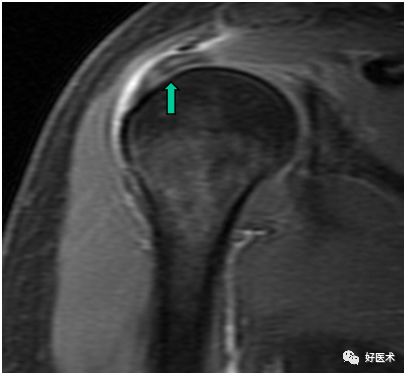

肩袖病变

-

Ⅰ期:T1W及PD上冈上肌在其附着处出现增高的信号影

Ⅱ期:肩袖变薄或不规则,肌腱内信号强度增加

Ⅲ期:肌腱的连续性中断或伴有增高的信号累及关节面